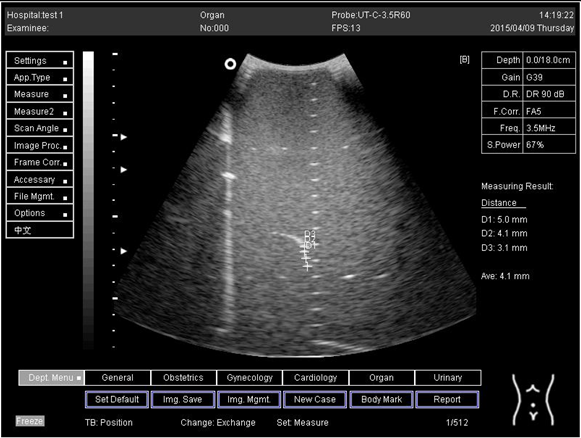

18.0Axial resolution

Biomimetics 07 00130 i027

D1 = 5.0

D2 = 4.1

D3 = 3.1

Lateral resolution

Biomimetics 07 00130 i028